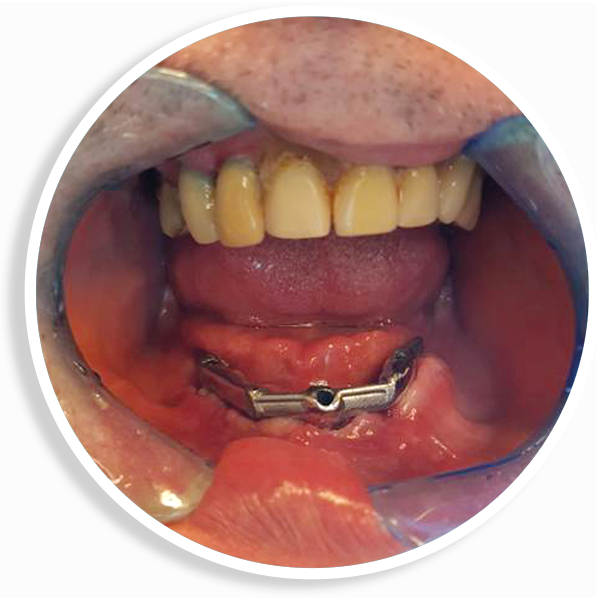

È una protesi completamente rimovibile e personalizzata, la cui stabilità è garantita dal posizionamento sull’arcata da riabilitare di due o quattro impianti collegati tra loro eventualmente da una barra. La protesi risulterà stabile perché agganciata proprio agli impianti o alla barra con attacchi particolari.